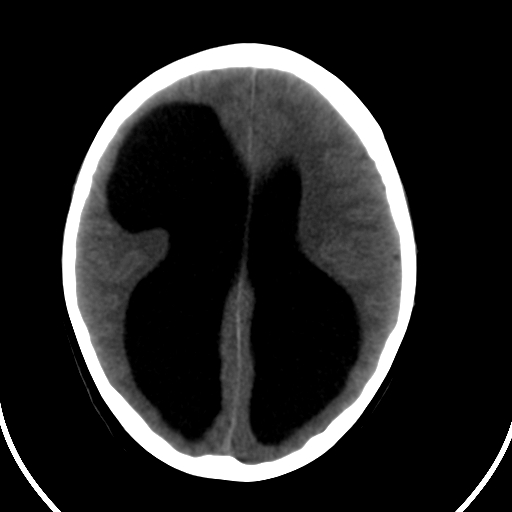

男,11岁

右额叶单发近圆形低密度影,周边光滑,与侧脑室相通,考虑为孔洞脑并阻塞性脑积水。

右额叶内见一边界清楚,脑脊液密度的囊腔,无灰质内衬,并与脑室相通,四室以上脑室系统高度扩张。诊断:先天性脑穿通畸形伴梗阻性脑积水

需要与脑裂畸形鉴别:可见单侧或双侧衬有皮层的脑裂伸入额顶叶的白质内并与脑室相通

脑穿通畸形并梗阻性脑积水.

脑穿通畸形囊肿脑积水